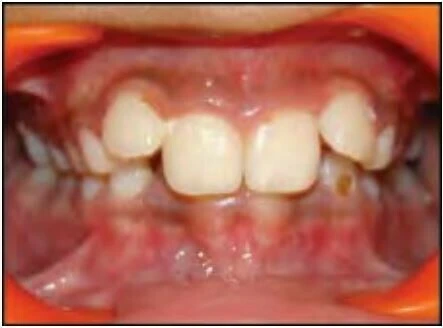

2.3 SAI KHỚP CẮN THEO MẶT PHẲNG NGANG

Trường hợp này bao gồm nhiều kiểu cắn chéo khác nhau. Thông thường các răng hàm trên nằm về phía ngoài so với các răng hàm dưới, nhưng đôi khi do cung răng hẹp hoặc vì một số lý do khác mà tương quan này bị xáo trộn. Chẳng hạn một hoặc nhiều răng hàm trên nằm về phía trong so với các răng hàm dưới, tình trạng này khác nhau về mức độ, vị trí và số lượng răng liên quan.